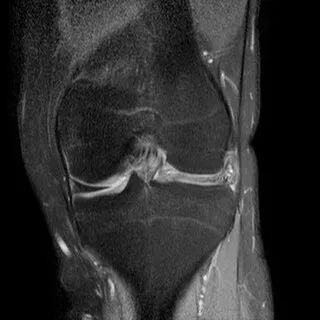

半月板撕裂定义与显示

1、半月板显示:以T2-WI加脂肪抑制为最好.2、半月板病变:最常见损伤是撕裂伤3、病因:慢性退变性撕裂和急性外伤性撕裂4、诊断方法:当半月板内出现线样高信号到达其游离缘或关节面时,即可诊断半月板撕裂5、病变信号变化:T1WI为线样稍高信号,T2(FS)或T2*WI信号更高6、半月板球形及线行高信号影未达关节面,为其慢性损伤或退行性改变(变性)7、MR诊断半月板撕裂的准确度达90-97%,特异性为94%,假阳性高于假阴性,主要是将膝横韧带与外侧半月板相邻的国肌腱鞘等误认为半月板撕裂.